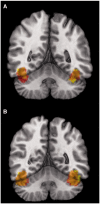

Both behavioral and neuroimaging evidence support a female advantage in the perception of human faces. Here we explored the possibility that this relationship may be partially mediated by female sex hormones by investigating the relationship between the brain's response to faces and the use of oral contraceptives, as well as the phase of the menstrual cycle. First, functional magnetic resonance images were acquired in 20 young women [10 freely cycling and 10 taking oral contraception (OC)] during two phases of their cycle: mid-cycle and menstruation. We found stronger neural responses to faces in the right fusiform face area (FFA) in women taking oral contraceptives (vs freely cycling women) and during mid-cycle (vs menstruation) in both groups. Mean blood oxygenation level-dependent response in both left and right FFA increased as function of the duration of OC use. Next, this relationship between the use of OC and FFA response was replicated in an independent sample of 110 adolescent girls. Finally in a parallel behavioral study carried out in another sample of women, we found no evidence of differences in the pattern of eye movements while viewing faces between freely cycling women vs those taking oral contraceptives. The imaging findings might indicate enhanced processing of social cues in women taking OC and women during mid-cycle.